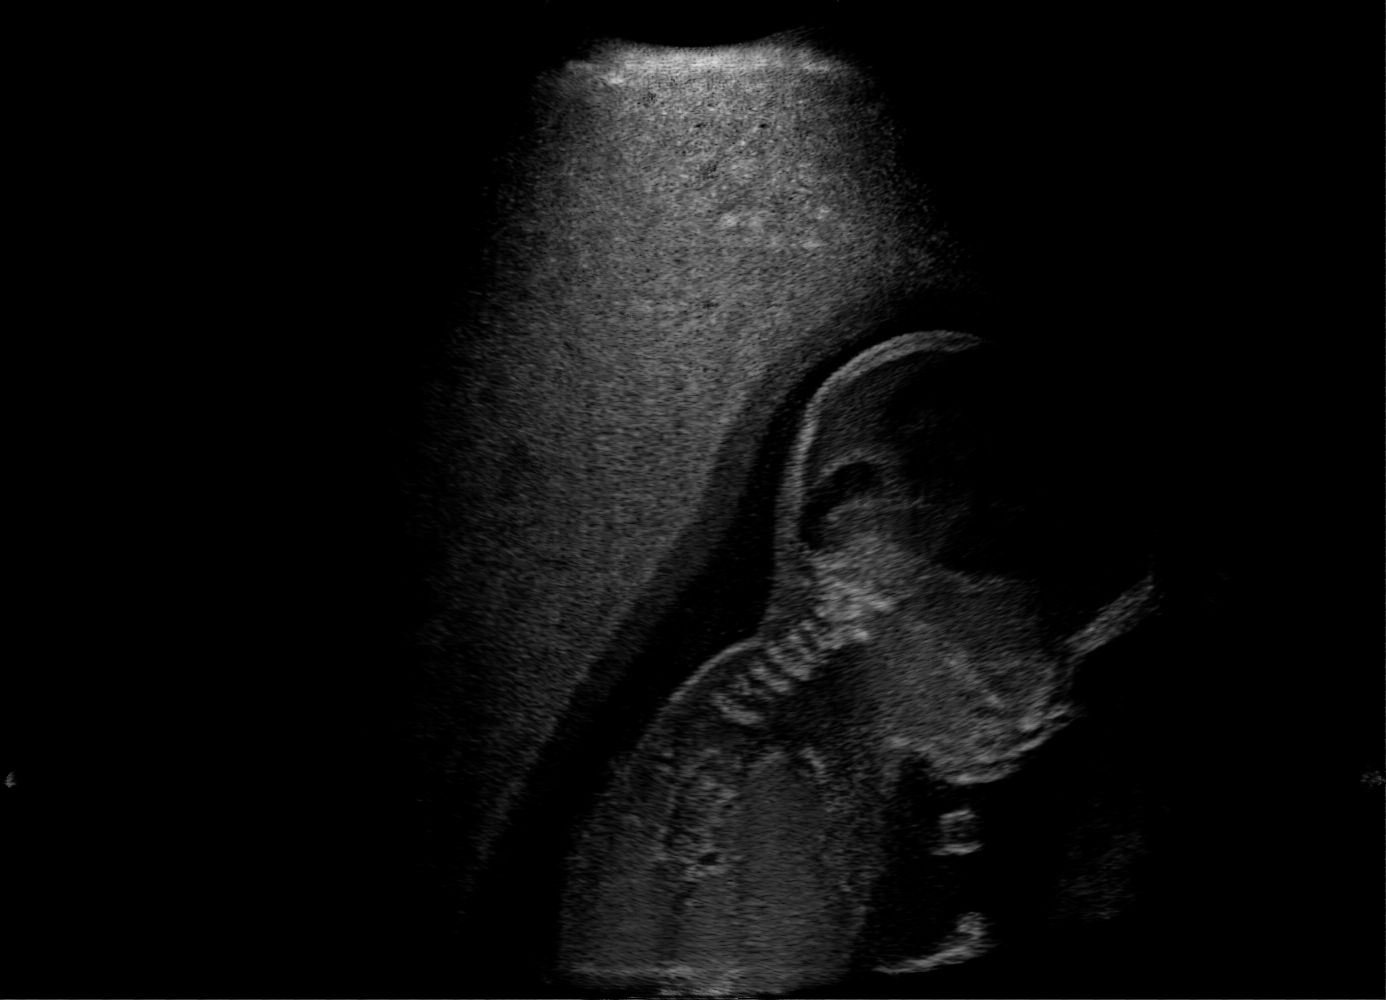

US images. For each regularly-sampled key frame of a simulated US fetal exam, paired low and high quality images are generated using two simulation passes: low quality images using one primary ray per US scanline and one elevational layer; and high quality images using 32 primary rays per scanline and three elevational layers [10]. Other simulation parameters are kept identical for both simulation passes, cf Table 1. Example B-mode images are shown in Fig. 1(a-b).

Qualitative Results. Fig. 3 shows a visual comparison of the three model variants on four examples. The baseline L2HM fails to preserve anatomical structures due to missing structural information in the input images. Resulting ambiguities in the network prediction cause artifacts such as blur in regions that feature fine details such as bones. Providing segmentation maps as additional input (L2HMS) greatly reduces such artifacts as shown in Fig. 3(c). However, L2HMS still struggles in modeling complex non-local features such as directional occlusion artifacts, note the lack of acoustic shadows in Fig. 3(c). In contrast, our final model L2HMSA is able to accurately synthesize these features and produces translations significantly closer to the target, as demonstrated in Fig. 3(d). In particular, our proposed model with segmentation and attenuation integral maps is able to recover both missing anatomical structures and directional artefacts.

Above image translation has been demonstrated on patches. For the entire field-of-view (FoV) US images, patch fusion from image translation of non-overlapping patches would cause artifacts at image seams. Averaging overlapping patches, on the other hand, would blur the essential US texture. Although seamless tiling of US images is possible using graphical models [3], this requires prohibitively long computation time. Herein, we instead directly apply our trained generator on full FoV low-quality images, since the generator is fully convolutional and thus can operate on images of arbitrary size. Fig. 4 shows two examples of translated images by L2HMS and L2HMSA, demonstrating direct inference on full FoV images. While anatomical structures are well preserved and the effect of attenuation integral map is apparent, speckle texture appearance is seen to degrade slightly especially in the top image regions, where the ultrasound texture looking particularly different due to focusing difference and near-field effects.

(a) Input

(b) L2HM

(c) L2HMS

(d) L2HMSA

(e) Target